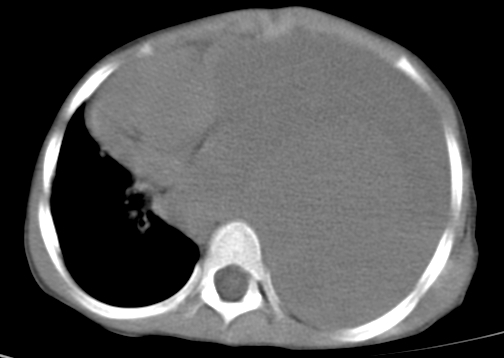

患儿 女 4岁,发热 咳嗽 胸透 考虑:左侧脓胸

左侧胸廓内见大量密实阴影,肺尖部尚有少量肺组织影,纵膈明显受压移位,肋骨未见明显受侵征象,虽然病人年龄较小,但如此大量的“积液”,还是要警惕,不同意一般感染,可结合穿刺脱落细胞学检查。

1)考虑左肺炎症感染。2)左侧大量胸腔积液。

左侧大量胸腔积液。

1)考虑左肺炎症感染。2)未经穿刺只能定左侧大量胸腔积液。

左侧大量胸腔积液;建议胸水检查。

左侧张力性大量胸腔积液压迫性肺不张、感染;建议治疗后复查。